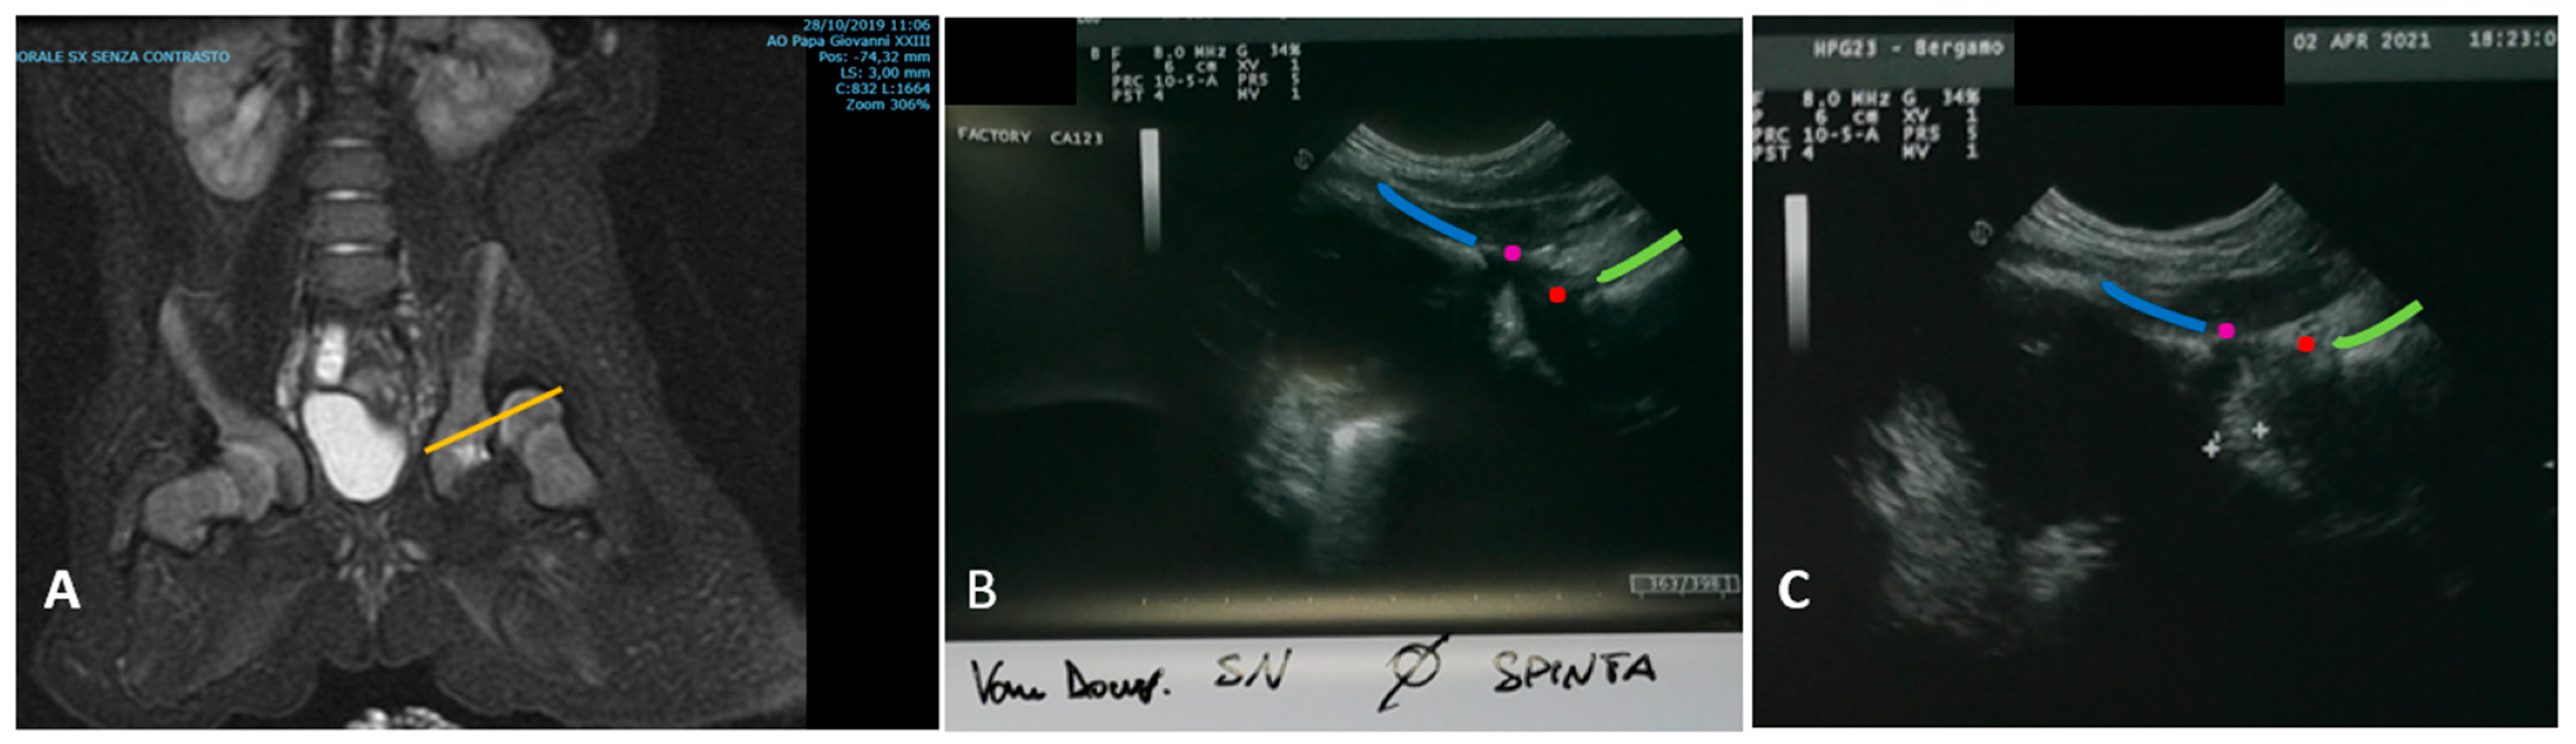

2. Materials and Methods